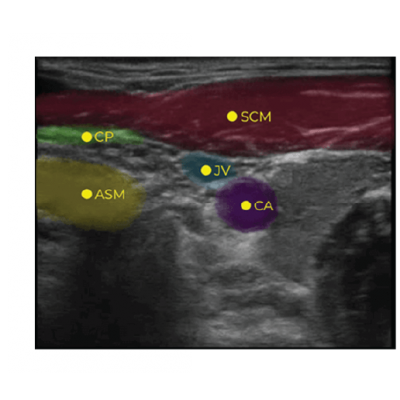

Nerveblox AI technology for ultrasound guidance is meticulously designed for anesthesiologists performing peripheral nerve block procedures and training. It is most valuable for applications requiring precision and those less frequent procedures that can be challenging due to their rarity – areas where AI capabilities outperform human attention. This versatility makes it an indispensable tool for highly skilled anesthesiologists who may require assistance with these uncommon procedures and peace of mind for image interpretation, especially regarding sonoanatomy.

Furthermore, our technology extends beyond anesthesiologists who are experts in ultrasound imaging. Anesthesiologists, including general practitioners, emergency medicine doctors, who may not possess specialized ultrasound training, can harness the power of our AI technology. Nerveblox provides standard, more accurate, and reliable peripheral nerve block guidance for them. This inclusivity ensures that anesthesiologists across all expertise levels can provide enhanced patient care through the utilization of advanced ultrasound technology tailored to peripheral nerve block procedures and training.